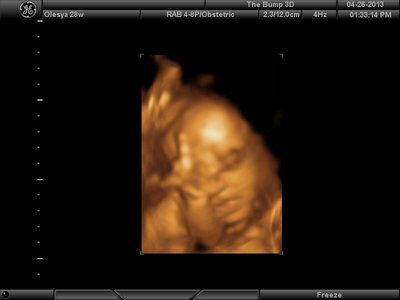

А я вчера на 3Д УЗИ ходила. Моя звезда закрывалась в еми 4мя конечностями. Просто пополам сложилась и спала себе сладко. УЗИстка провела со мной час, кое-как расшевелили маленькую, но ручка была постоянно на мордашке и засыпала она почти сразу снова. Я и на мяче прыгала и живот трясла. В конце более-менее фото вышли, но качество меня не порадовало. Возможно фри оф чардж еще раз переделают. Со средней фотки были отличного качества, а эти сплошное разочарование. Вот тут что-то более-менее еще. Главное пальчик оттопырила так смешно, мол минуточку. Вообще немного жутковатые фотки..хаха

| Вложения: |

image.jpg [ 47.86 КБ | Просмотров: 1458 ]

Еще одна, качество ужасное..

image.jpg [ 60.32 КБ | Просмотров: 1455 ]